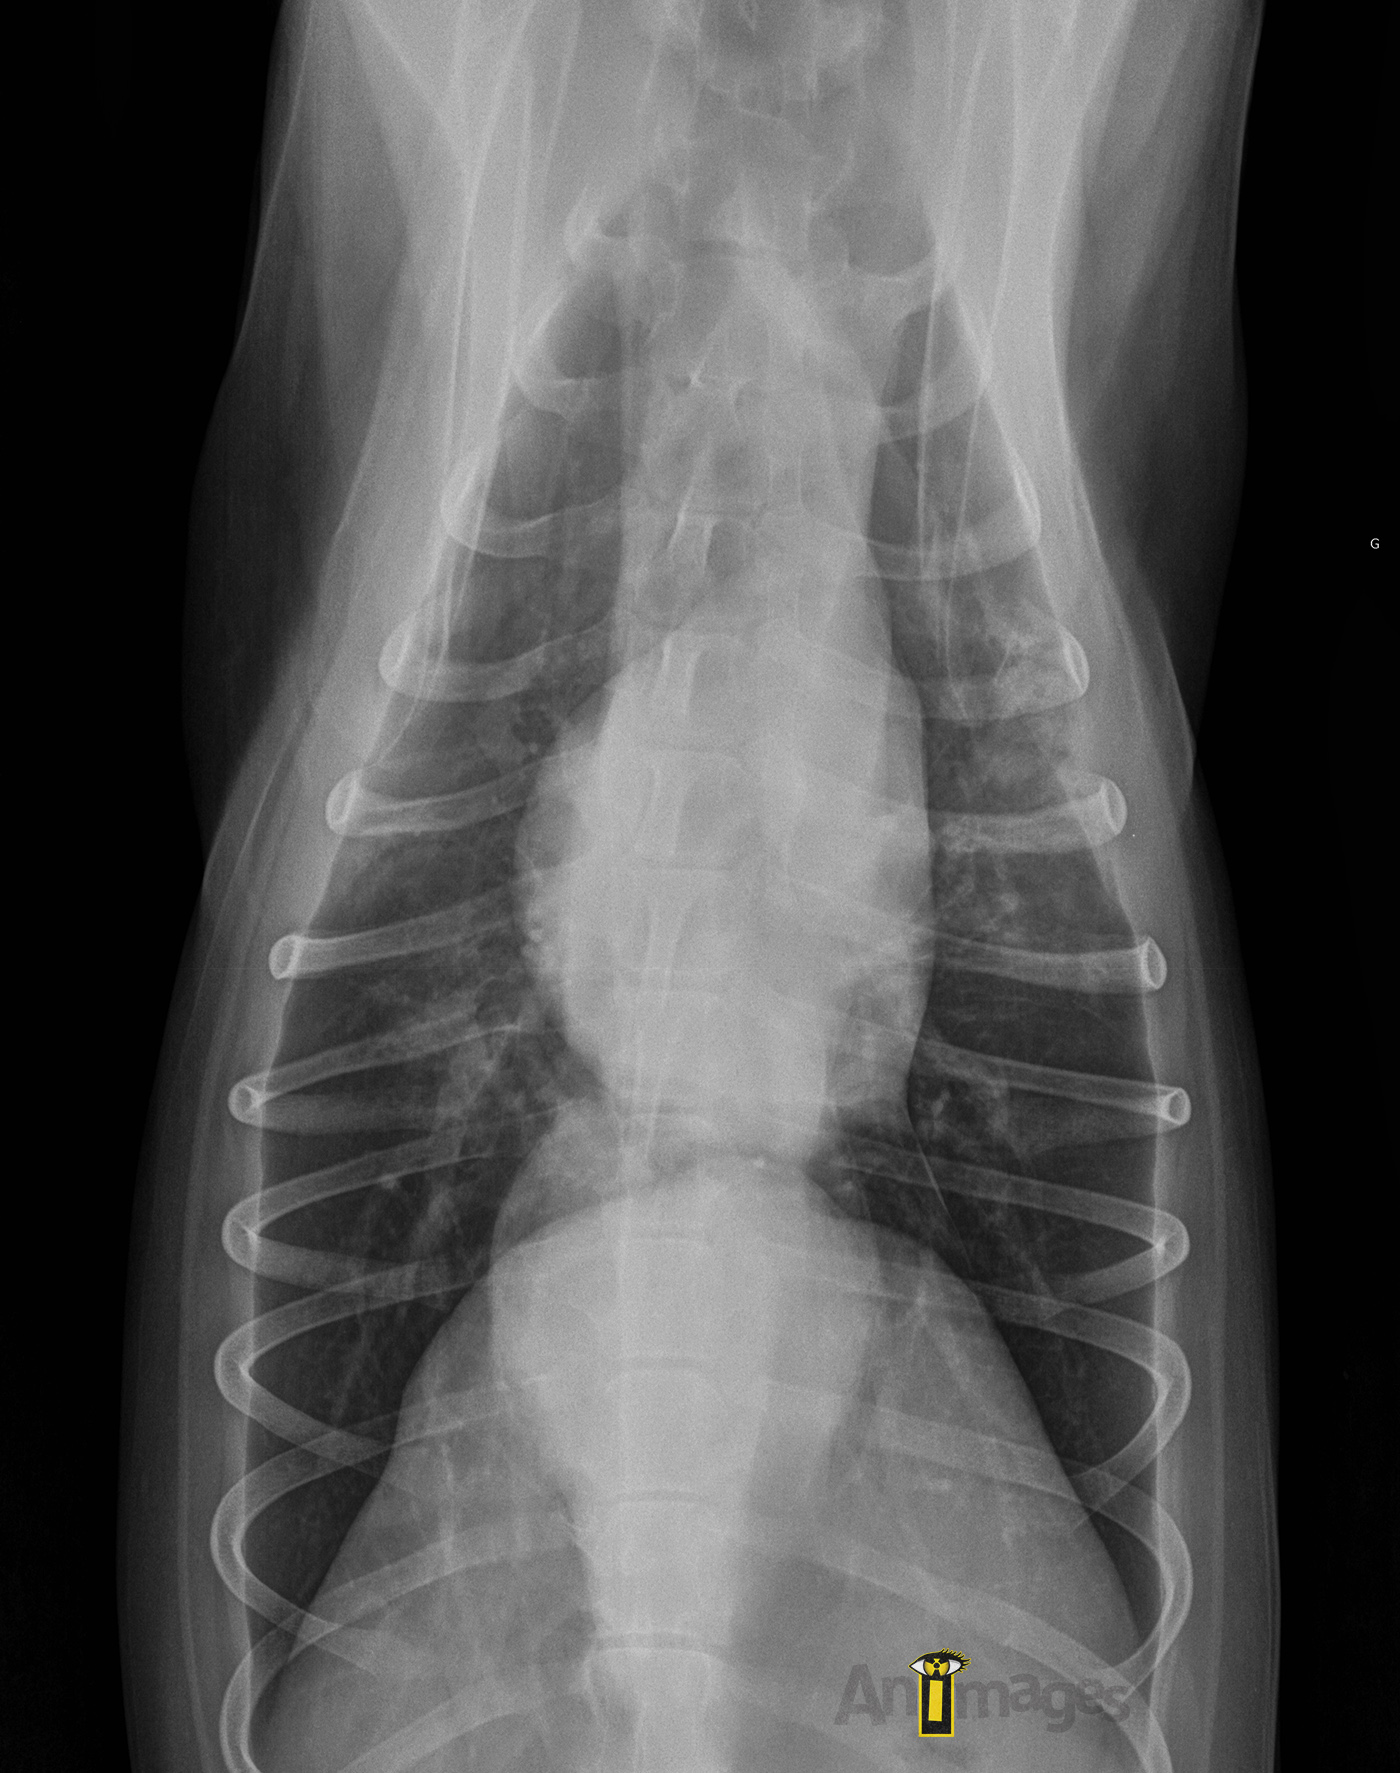

Ventrodorsale